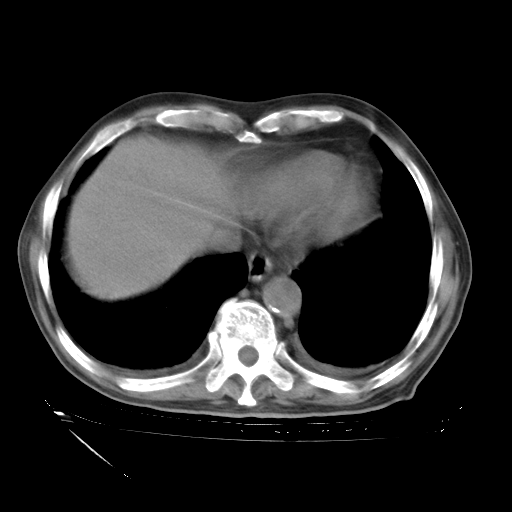

经过24天治疗,岳父的病情基本稳定。生活基本可以自理,可以下床活动。呼吸困难早已消失。体温基本正常。

只是甲强龙用80mg时血小板升到正常,改为60mg后又降到63×10*9/L。

主要治疗甲强龙80mg×14天,60mg×10天;同时抗结核(异烟肼+利福平+乙胺丁醇)。环磷酰胺0.1 tid 10天。

特别感谢胡教授、高管、桃子版主给出关键的治疗建议。桃版把所有肺部影像和全部临床资料请所在医院呼吸科、感染病科、结核科、临床免疫科专家会诊。临床免疫科专家制定了完整的治疗方案。